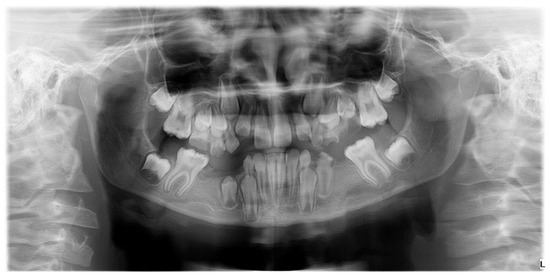

Numerical anomalies (agenesis, supernumerary teeth) did not account for the presence or absence of wisdom teeth. The diagnosis was made following clinical examination, anamnesis, and medical history, with dental extractions excluded. Numerical anomalies were confirmed radiographically, based on an orthopantomogram taken with Pax Flex 3D +, Vatech X-ray machine, VATECH Dental Manufacturing Ltd., Sutton, UK, with an exposure time of 12.9 s, 80 kVp, and 9.0 mA (Figure 5).

Figure 5.

Orthopantomogram of a patient with mixed dentition, clinical diagnosis of MIH, and radiographically certified hypodontia.